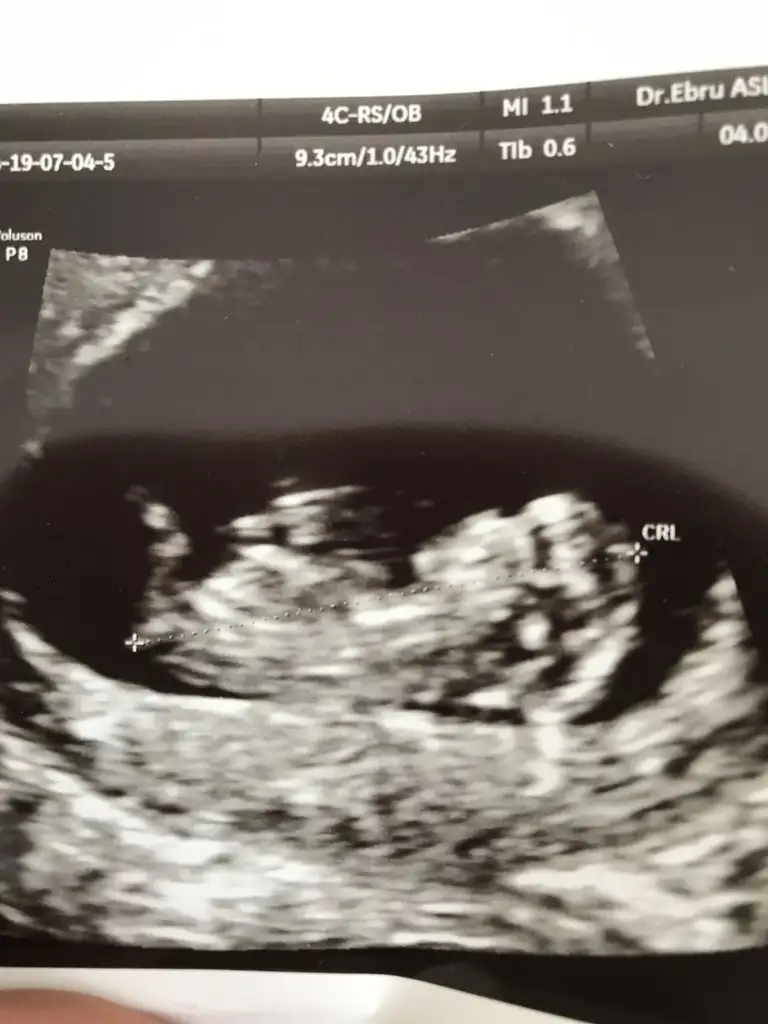

Benim bütün kontrollerimde usg ye göre doğum 10 Ocak. Adete göre 13. Hangisini baz alsam. Çatlatma iğnesiyle hamile kaldığıma göre ilkini baz alayım değil mi?